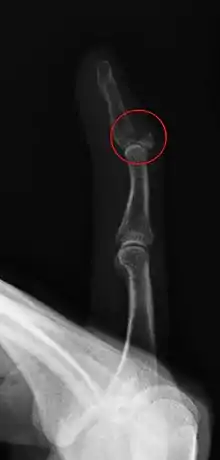

كسر انقلاع الأحدوبة الظنبوبية

إن كسر انقلاع الأحدوبة الظنبوبية هو عبارة عن فصل جزء من الأحدوبة الظنبوبية لقصبة الساق أو فصلها بأكملها. و يحدث هذا نتيجة للتقلص الشديد في عضلات الفخذ، وفي أغلب الأحيان يكون نتيجة القفز المرتفع. ويمكن علاج الكسور الجزئية باستخدام الأساليب التقليدية (الراحة، الثلج، الضغط، والارتفاع) ،ولكن غالبا ما تتطلب الكسور الكاملة عملية جراحية لتدبيس الأحدوبة الظنبوبية في مكانها مرة أخرى. يحدث كسر الأحدوبة الظنبوبية في الغالب للمراهقين الذين يمارسون الأنشطة الرياضية بشكل كبير، وقد أظهرت العديد من الدراسات أن تاريخ داء التَّنَكُّسُ العَظْمِيُّ الغُضْروفِيُّ لأُحْدوبَةِ الظُّنْبوب (التهاب الرباط الرضفي) مرتبط بالكسور.